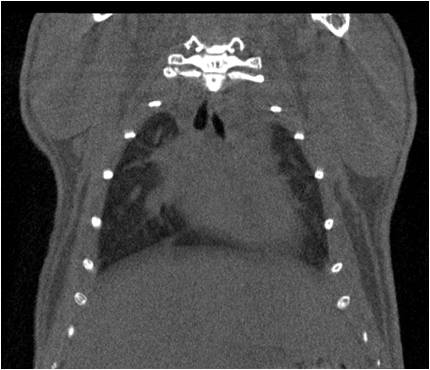

心血管

胸部和心血管的層析成像 胸部和心血管的3D圖像

能進(jìn)行心臟研究成像,包括心梗、心肌肥大、動(dòng)脈粥樣硬化、心臟血管病變等研究,可獲取舒張期及收縮期心臟體積參數及左心室射血分數等功能參數;

能進(jìn)行全身血管成像研究,獲得高分辨率的血管造影影像;